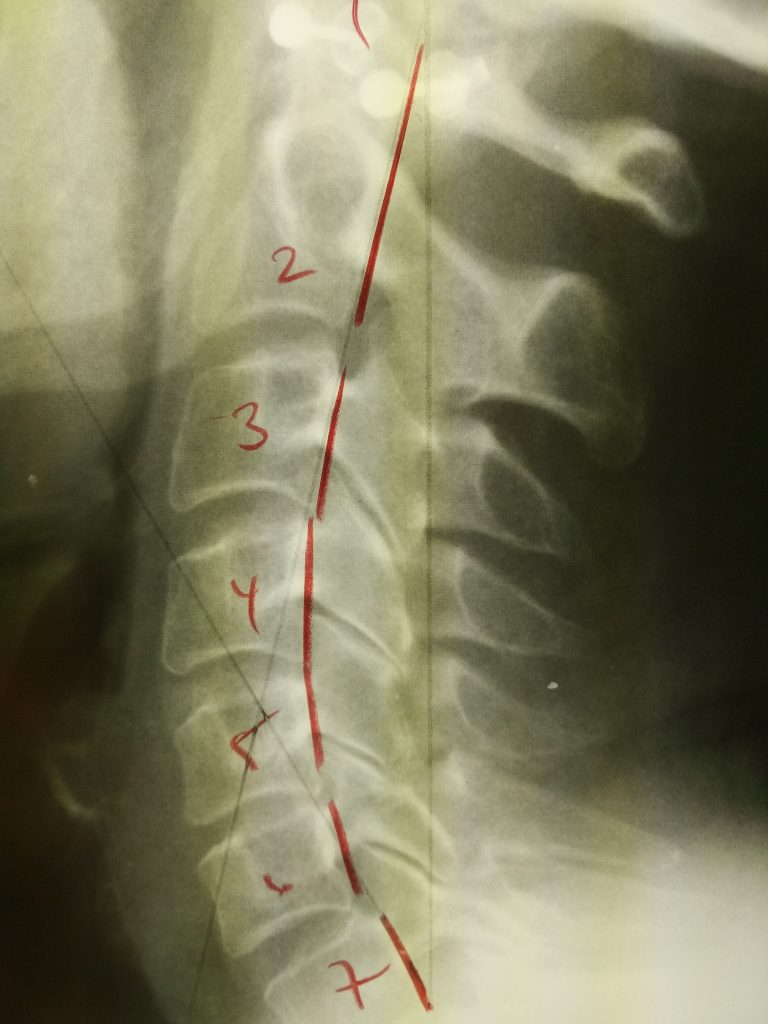

Scoliosis posture and spinal curve support in Newmarket Ontario

Can You Do Anything for Scoliosis?

We see many kids and adults who come into our Newmarket chiropractic office wondering if there is anything that can be done to help with scoliosis.  They have been told to just “watch and wait”.  ...